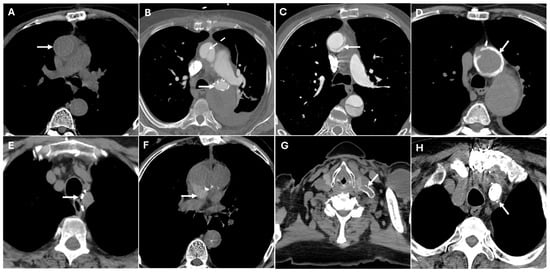

| Coronary Artery Complications | Coronary ostial obstruction | Narrowed or occluded ostium, diminished contrast opacification | Can lead to myocardial infarction |

| Graft Dehiscence and Leaks | Poor anastomotic integrity, infection, mechanical stress | Contrast extravasation at anastomotic sites, widened mediastinum, disrupted graft margins | Massive hemorrhage |

| Paravalvular Leak | Suture failure, prosthesis malalignment | Contrast extravasation around prosthetic valve annulus | High rupture risk |

| Pseudoaneurysm | Suture failure, infection, chronic mechanical stress | Contrast-filled sac adjacent to graft, narrow neck | High rupture risk |

| Perigraft Fluid Collection and Infection | Post-surgical infection | Rim-enhancing fluid collections, intrinsic air | Can progress to graft infection and sepsis |

| Pericardial Effusion and Tamponade | Post-surgical tamponade | Fluid collection in pericardial sac, cardiac chamber compression, septal bowing | May impair cardiac function |

| Endoleaks (TEVAR) | Incomplete sealing, graft migration | Persistent contrast enhancement outside stent graft lumen | Can lead to aneurysm expansion and rupture |

| Aorto-Esophageal or Aorto-Bronchial Fistulas | Erosion of graft into adjacent structures | Contrast extravasation into esophagus or bronchial tree, adjacent air | Massive hemorrhage |